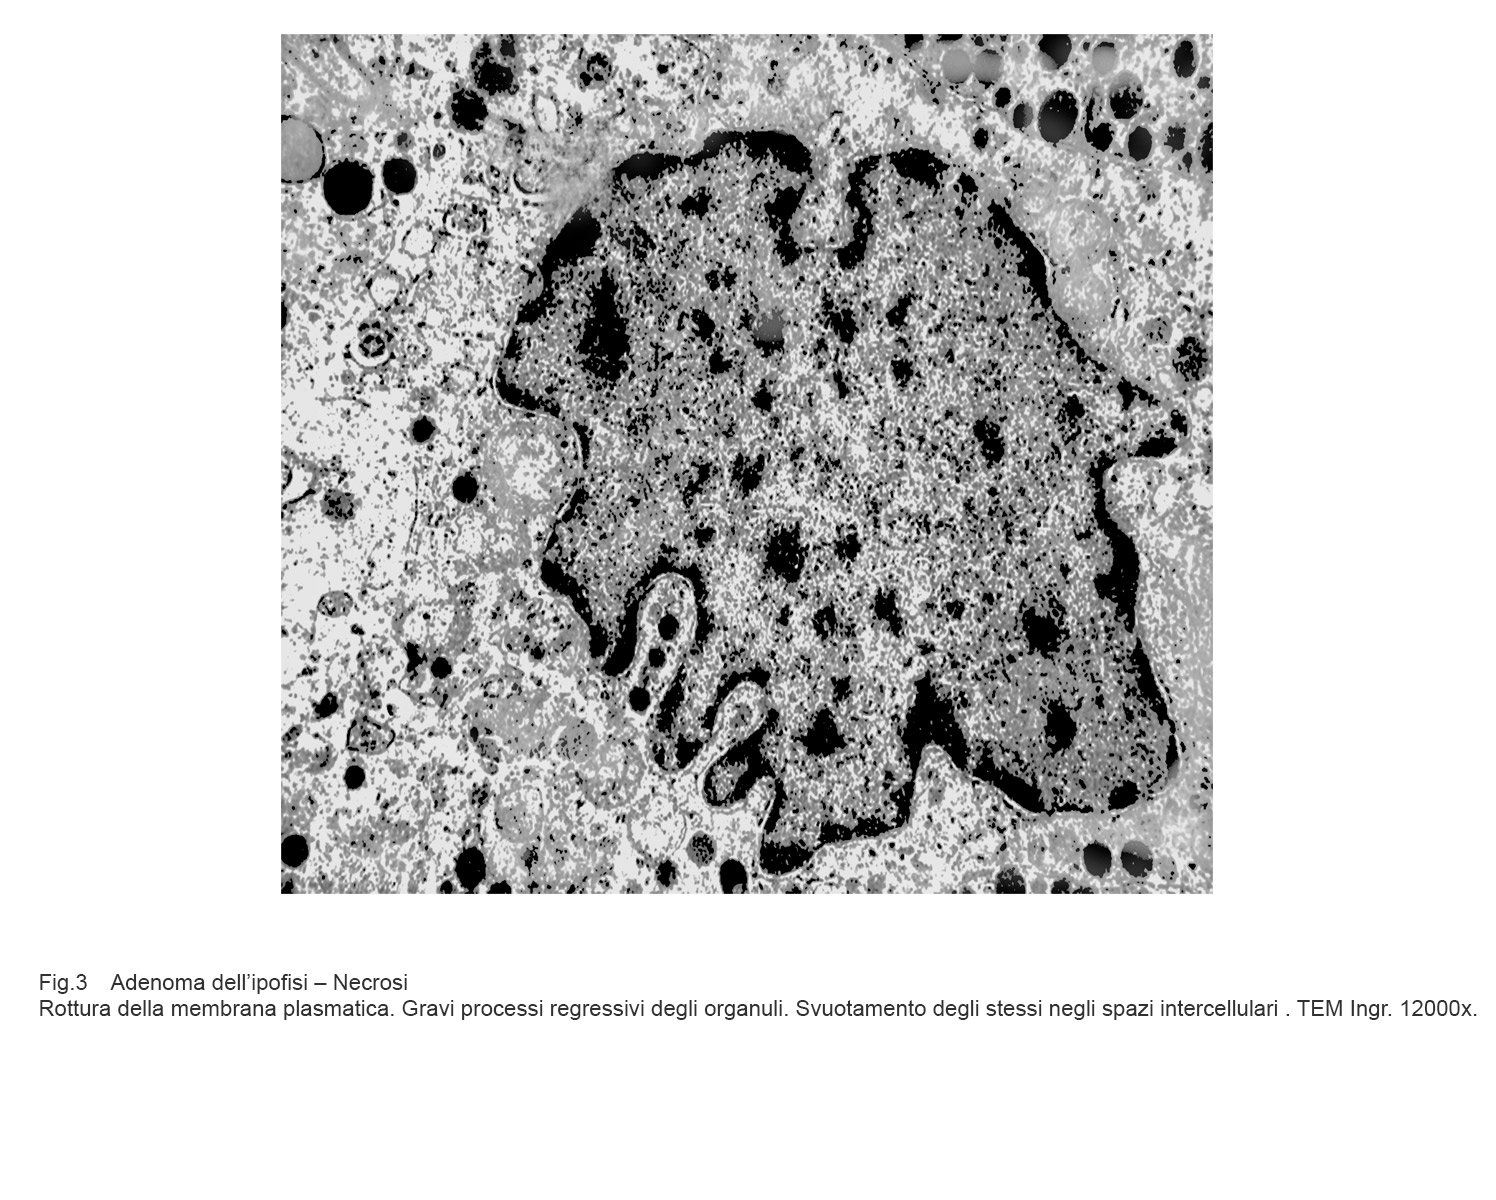

La necrosi è un evento non programmato di morte cellulare; essa si manifesta attraverso fasi non controllabili di destrutturazione della cellula fino alla sua lisi.

Si ha il quadro di un processo vacuolare irreversibile pre-necrotico con disaggregazione dello assetto degli organuli intracitoplasmatici, grave rigonfiamento dei mitocondri, dilatazione abnorme delle cisterne del retico endoplasmatico, perdita dei ribosomi, disgregazione del nucleo per rottura della membrana nucleare.

Tali eventi sono progressivi, si condizionano reciprocamente e si concludono con la frammentazione delle substrutture, rotture della membrana plasmatica e sversamento del contenuto negli spazi intercellulari.

Fig.3  Fig.4